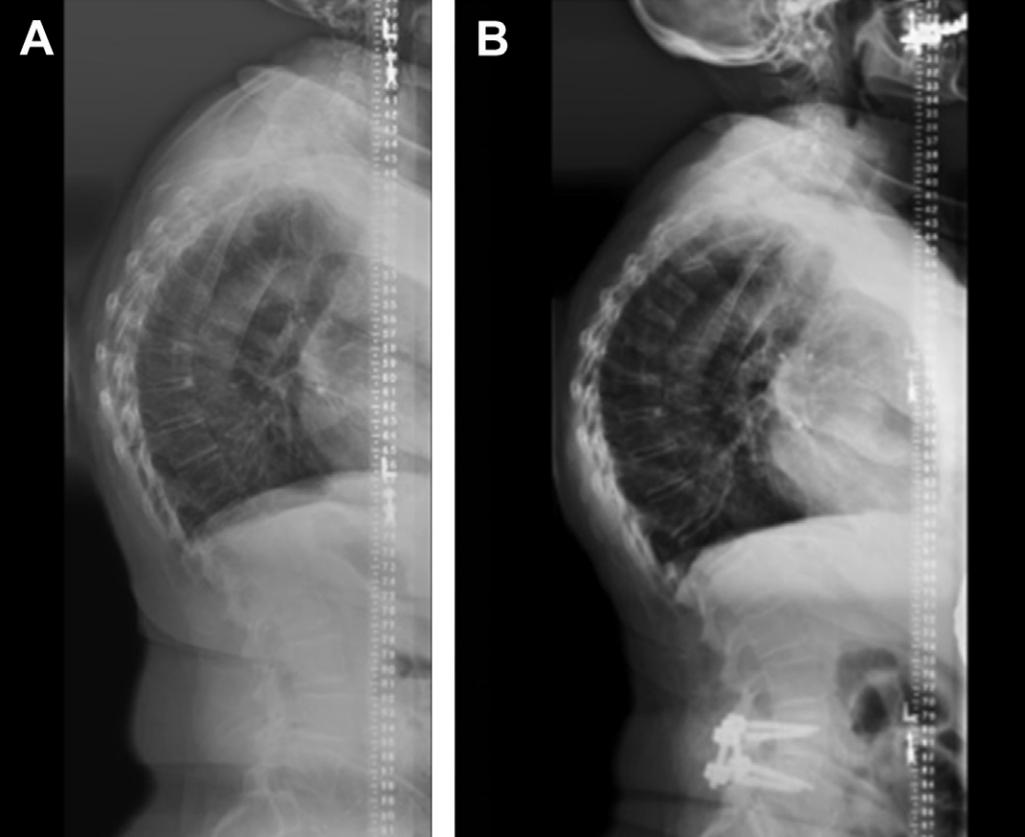

图:75岁妇女,术前(A)L4-5退行性腰椎滑脱,下肢放射性疼痛;融合手术后(B)症状缓解。